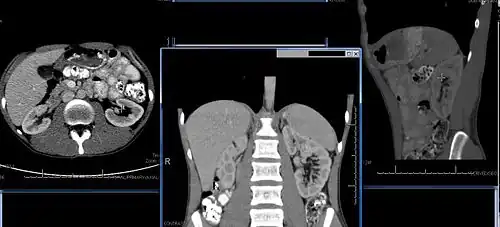

Chronic kidney disease (CKD) has been recognized as a leading public health problem worldwide. The global estimated prevalence of CKD is 13.4%, and patients with kidney failure needing renal replacement therapy are estimated between 5 and 7 million.[6] Procedures used in the management of kidney disease include chemical and microscopic examination of the urine (urinalysis), measurement of kidney function by calculating the estimated glomerular filtration rate (eGFR) using the serum creatinine; and kidney biopsy and CT scan to evaluate for abnormal anatomy. Dialysis and kidney transplantation are used to treat kidney failure; one (or both sequentially) of these are almost always used when renal function drops below 15%. Nephrectomy is frequently used to cure renal cell carcinoma.

Renal ultrasonography is essential in the diagnosis and management of kidney-related diseases.[49] Other modalities, such as CT and MRI, should always be considered as supplementary imaging modalities in the assessment of renal disease.[49]